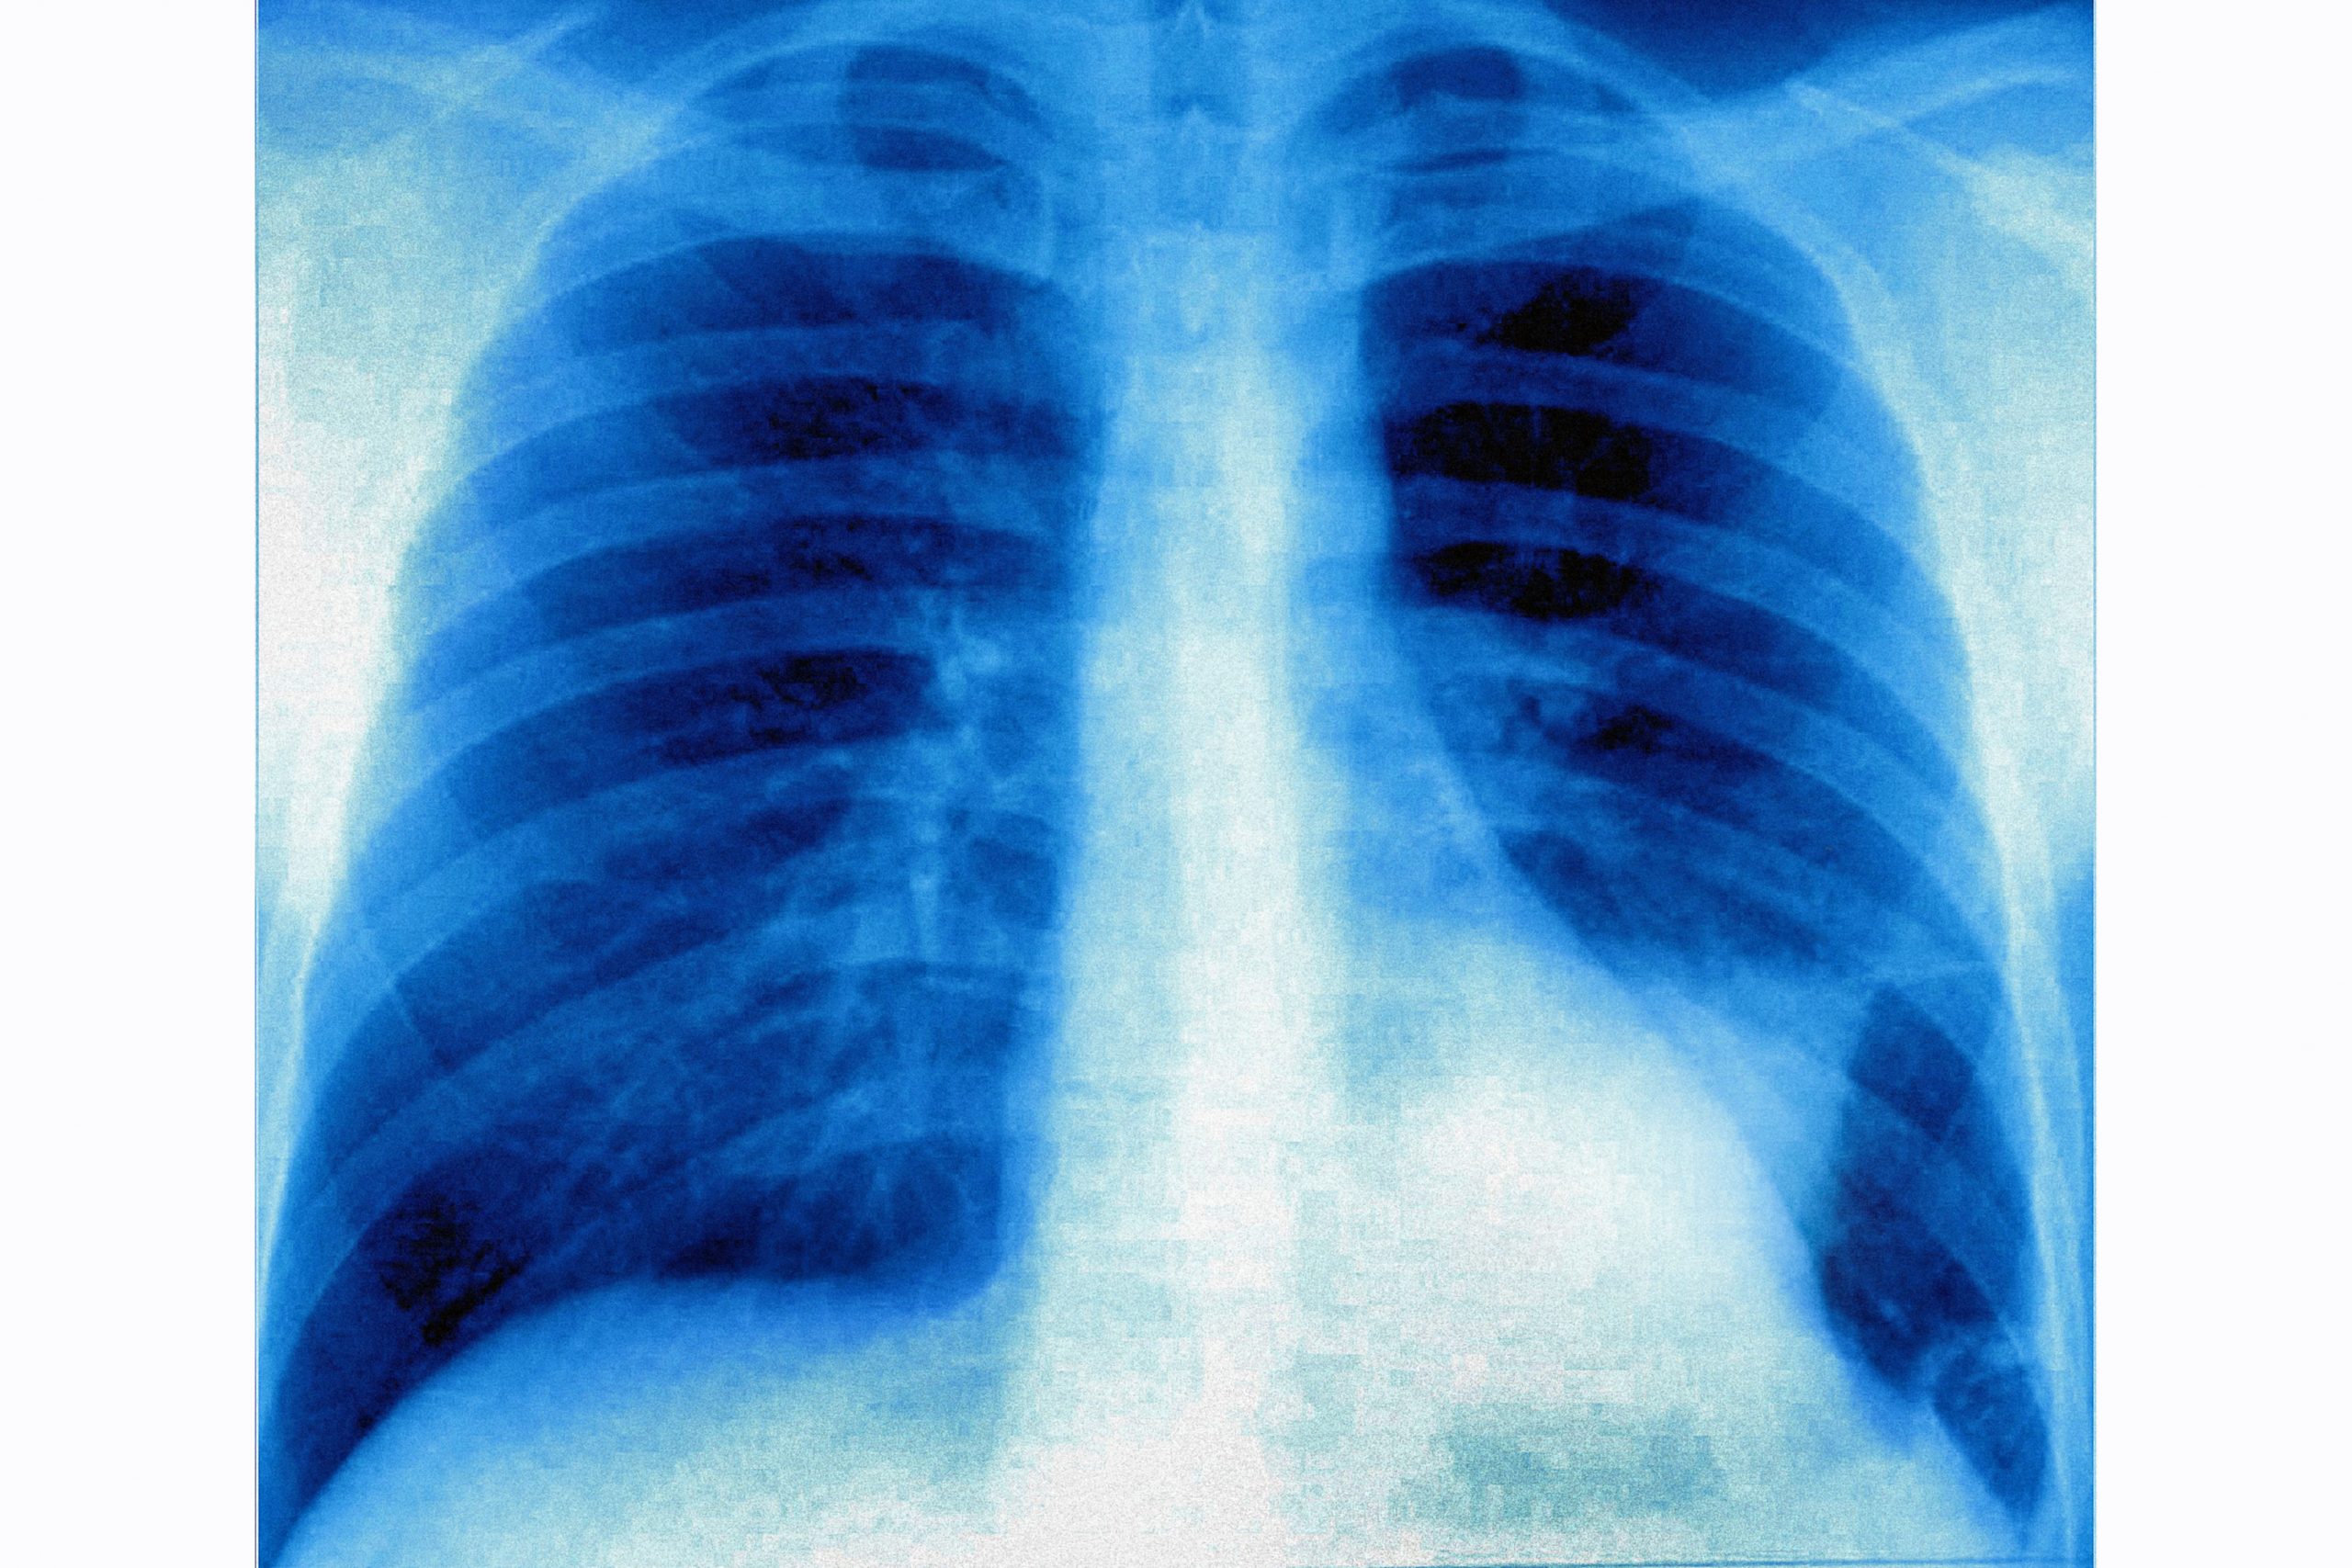

Рак легкого в левой легочной доле, видимый на фронтальном рентгене грудной клетки. (Фото: BSIP/Universal Images Group через Getty Images)